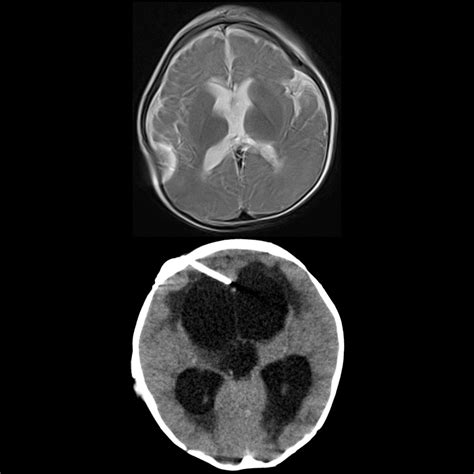

Hydrocephalus is a condition characterized by the accumulation of CSF in the brain, leading to increased intracranial pressure. This can cause a variety of symptoms, including headaches, nausea, and cognitive impairments. A VP shunt is a surgical solution that helps manage this condition by redirecting the excess fluid to the abdomen, where it can be absorbed naturally.

The VP shunt consists of several components:

• A catheter placed in the ventricles of the brain to drain the CSF.

• A valve that regulates the flow of CSF.

• A distal catheter that directs the fluid to the peritoneal cavity.